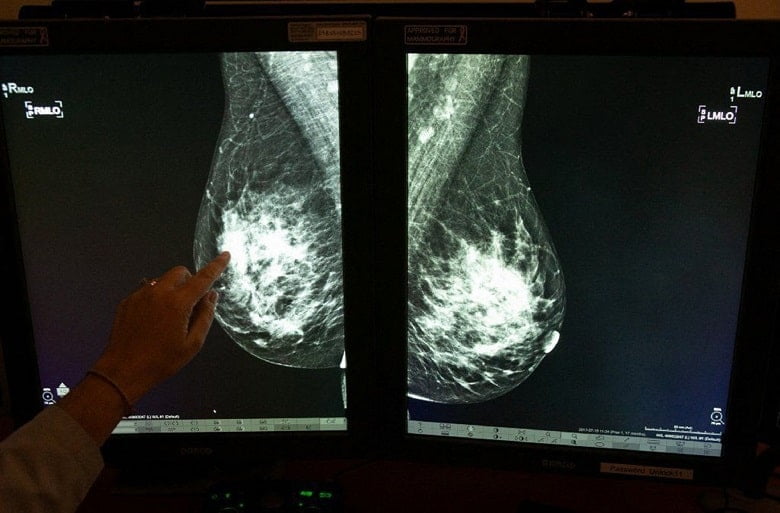

به طور سنتی، تراکم پستان با ارزیابی مقدار بافت در ماموگرافی اندازه گیری می شود. سیستم گزارش تصویری و پایگاه داده تصویربرداری پستان که یافتههای ماموگرافی را گزارش میکند، همچنین شامل اطلاعات مربوط به تراکم پستان است و سینهها را به چهار گروه طبقهبندی میکند: مناطق عمدتاً چرب، پراکنده، متراکم ناهمگن یا بسیار متراکم

در ماموگرافی هم بافت متراکم و هم سرطان سفید به نظر می رسند، بنابراین مانند تلاش برای یافتن یک گلوله برفی در طوفان برفی است. هنگامی که از سونوگرافی استفاده می شود، سرطان سیاه و بافت متراکم سفید به نظر می رسد و سرطان ها را آسان تر می بیند. از آنجایی که غربالگری ماموگرافی در اسکن بافت متراکم پستان موثر نیست، معرفی تصویربرداری سونوگرافی تکمیلی گام بعدی منطقی خواهد بود. افزودن یک سونوگرافی خودکار سه بعدی پستان برای غربالگری سرطان سینه نسبت به استفاده از ماموگرافی به تنهایی برای این گروه از زنان موثرتر است.